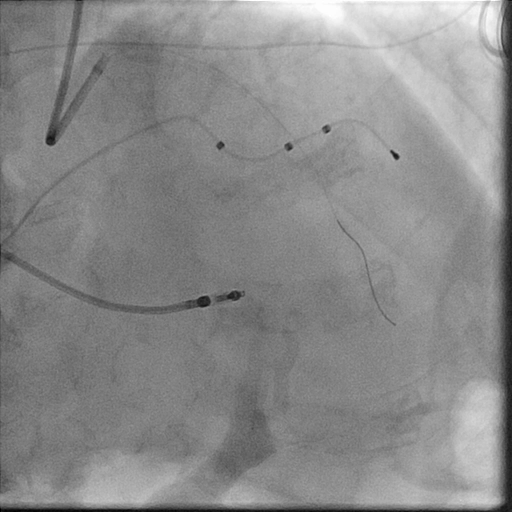

In the LightLab case, pre-PCI angio assessment and planned treatment approach (left image) was changed after performing pre-PCI OCT (right image).

The impactful changes include:

- Severity of lesion calcification angiographically underestimated

- Vessel preparation strategy updated to Non-Compliant Balloon and Rotational Atherectomy instead of using the Compliant Balloon

- Stent size changed by additional 6 mm in size from the originally planned by angio assessment

Morphology:

Calcified Mid LAD lesion (Type B)

Haemodynamically significant

Length:

30 mm

Diameter:

3.0 mm Distal, 3.5 mm Proximal

Vessel Prep Planned: Compliant Balloon

Treatment planned: 3.0 mm x 32 mm stent

38 mm

2.82 mm Distal EEL, 3.75 mm Proximal EEL

Minimum Lumen Area: 2.3 mm²

OCT Vessel Prep Planned: Non-Compliant Balloon, Rotational Atherectomy

Treatment planned: 3.0 mm x 38 mm stent